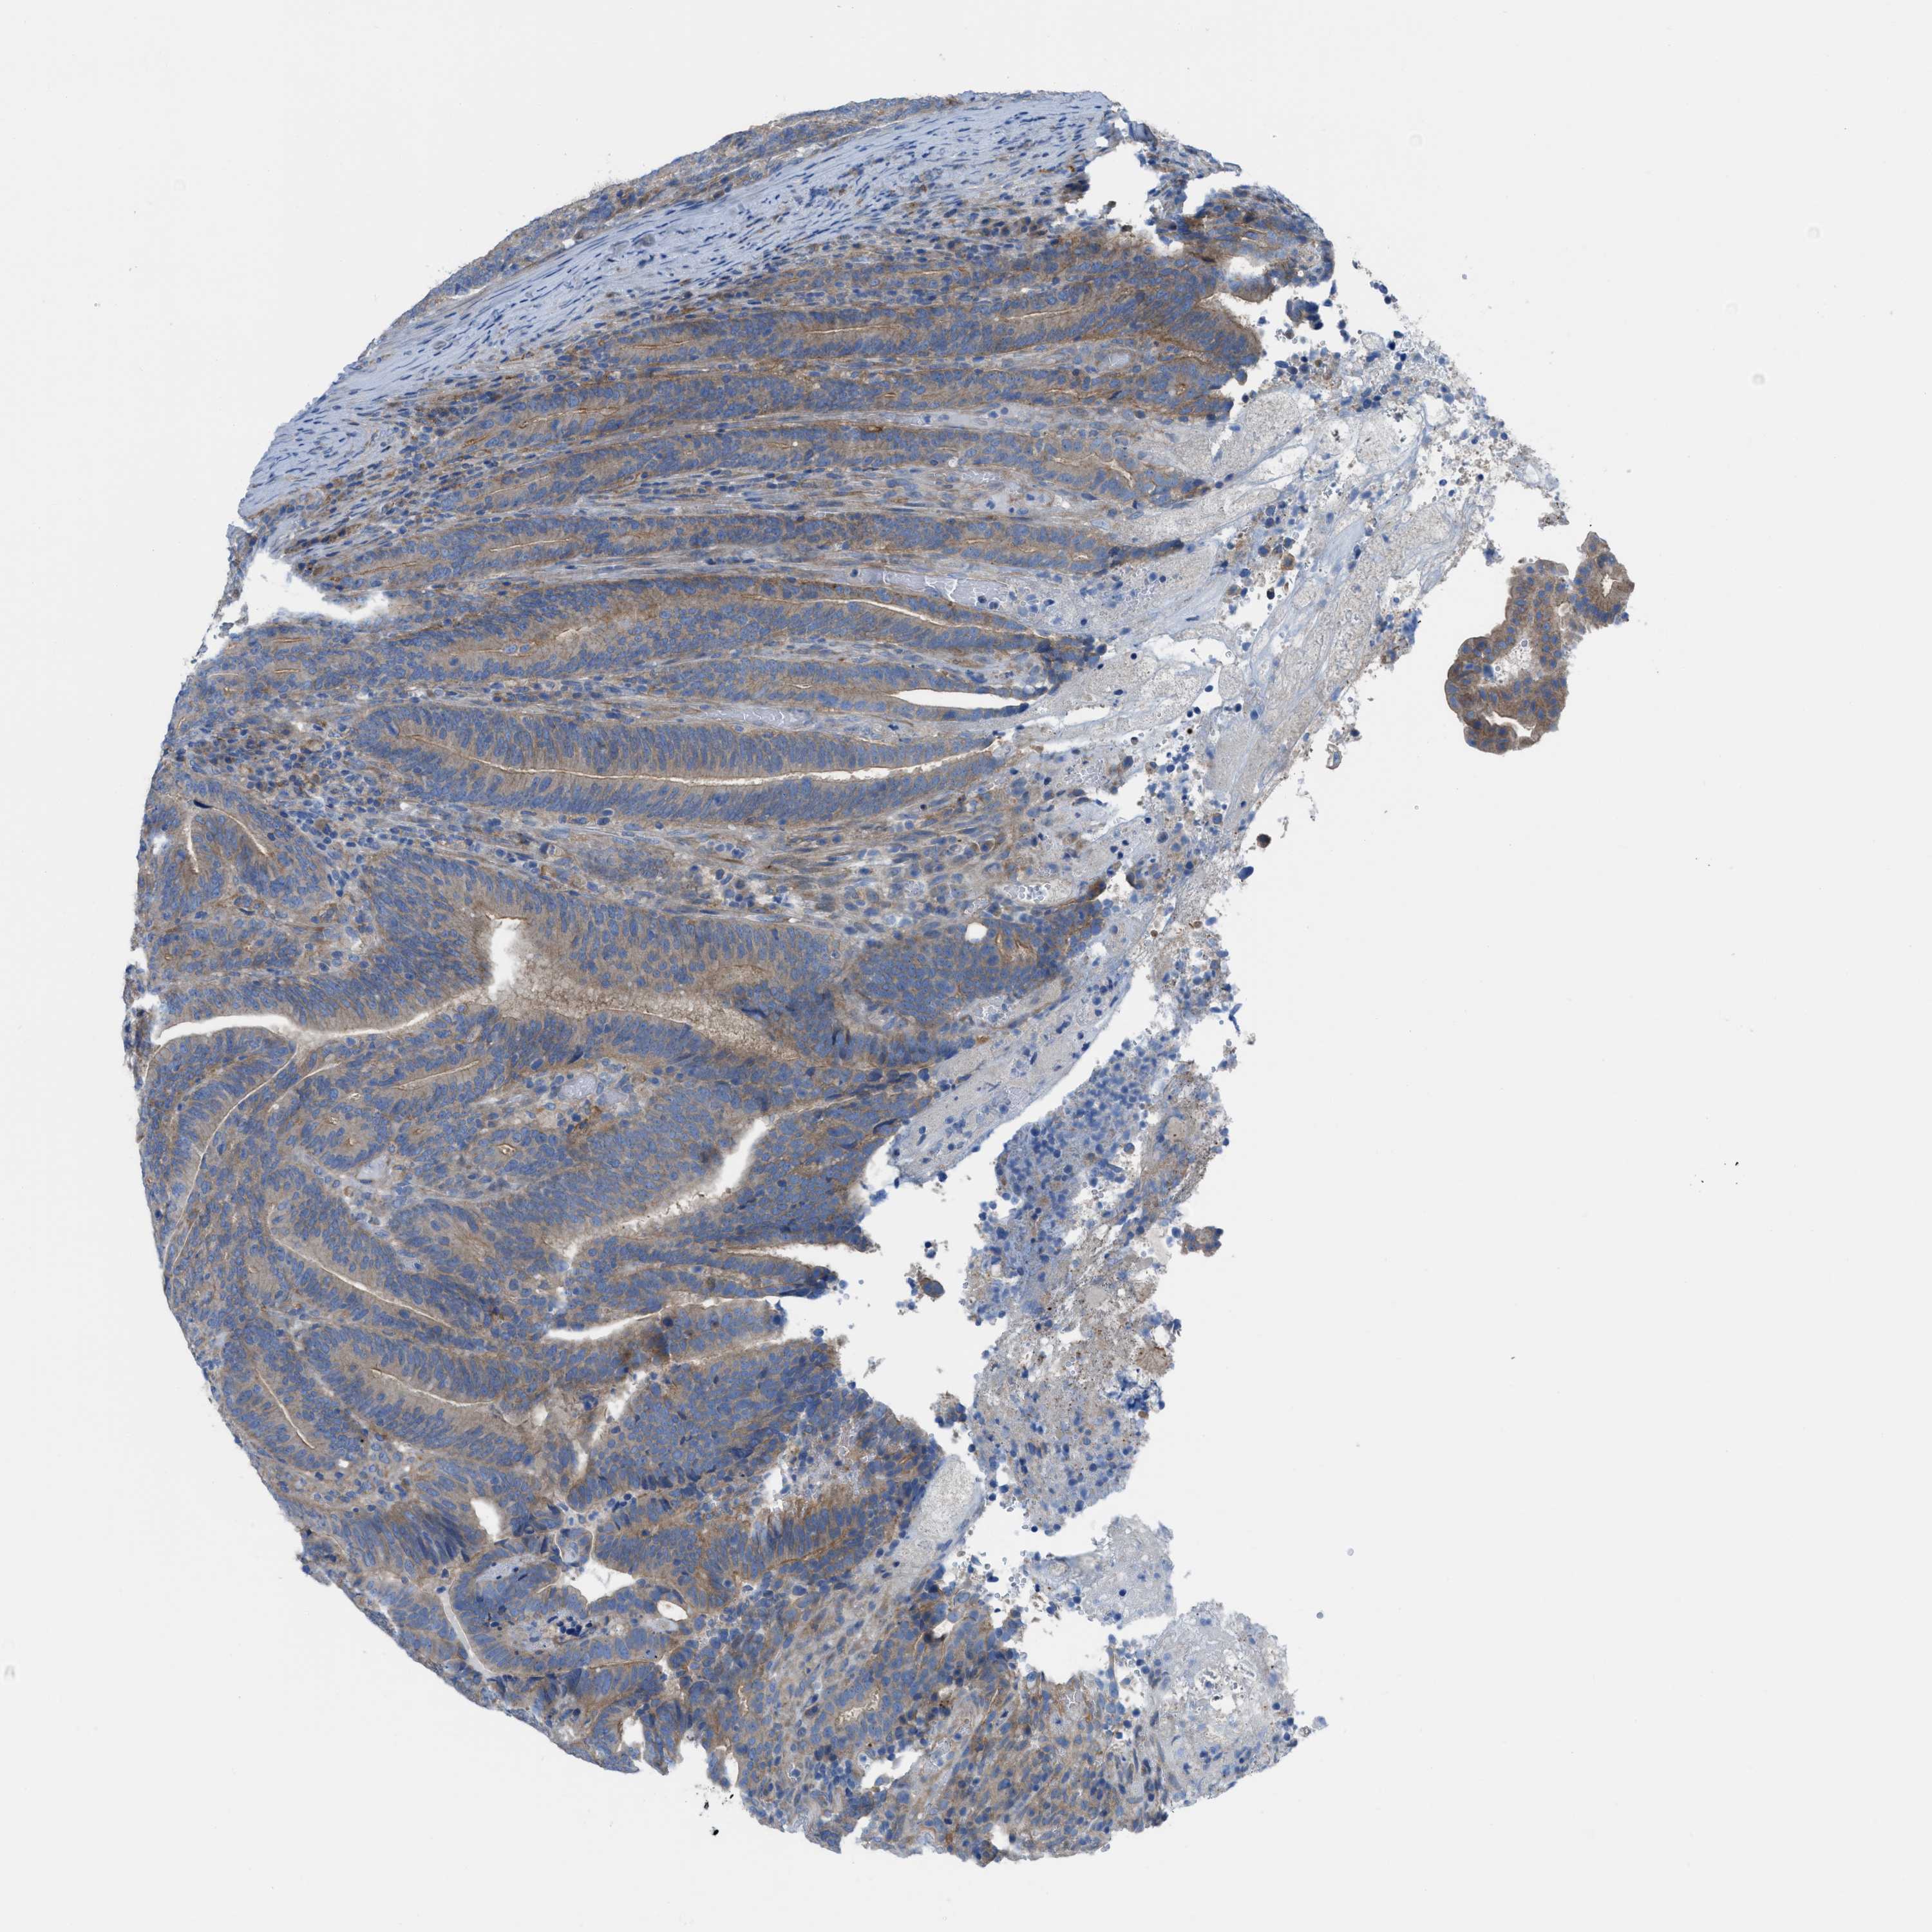

CANCER COLORECTAL CANCER Show tissue menu

Colorectal cancer

Human cancer

Colon adenocarcinoma